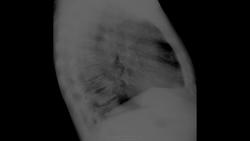

Метастазы в ребра? Такое вижу впервые...

коллега, почему только в ребра?  по-вашему, с легкими все хорошо?    я за множественные мелкие метастазы в легкие и ребра.

Тут правда только одно ребро справа. Интересно..., тоже метастазы?

Дак и позвонки весьма смутительные..., только вот векторе ли метастазов?

Но ведь простата может "насыпать " и в ребра, и в позвонки...

+1, тут не только ребра, легкие тоже

Да, и лёгкие , и кости.

Вид другой, у мочевого пузыря мтс остолитические/или смешанные, у простаты - бластные, а также динамика; и в легкие простата редко метастазирует.

Почему сразу метастазы? Может сначала интерстициальный отек легких.

При отека обычно подчеркнута правая горизонтальная междолевая плевра, да и ведь это не просто так - отек лекгих, должна быть клиника отека.

Пациента вижу впервые - архива нет.

Жалобы только на затрудненное мочеиспускание (только на эту жалобу он пожаловался мне при разговоре). Клиники отека точно нет. Самочувствие хорошее, и вообще на вид вполне здоров :-) Из всех назначенных ему исследований и анализов сначала пришел на флюшку, поэтому ничего больше сказать не могу и склоняюсь именно к простате. Вот так коллеги.

На фоне таких плотных и "рябых" ребер легкие могут быть тоже усеяны. Вполне может быть и там и там и еще в позвонках...и наверняка еще где-то. Но вот четко остеобластические я вижу в ребрах причем в огромном количестве.

Субъёктивно, на второе место в дифряду, поставил бы болезнь Педжета!

У меня были почти такие же легкие, у мужчины аденома простаты, сделали флюшку, нормально, только усиление рисунка, он отправился на лечение, через 2 недели лечения така же картина, написали мтс в кости и лимфангоит, на этом фоне не исключили в легких мтс.